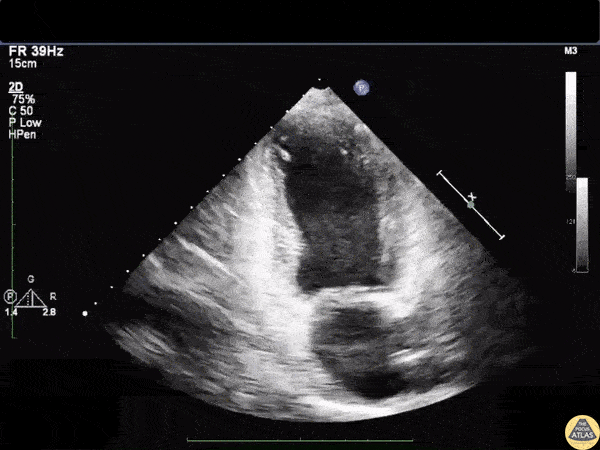

Left Ventricular Dysfunction - Takotsubo Cardiomyopathy on Apical Two Chamber View

Apical 2 chamber view showing akinesia of the apical walls characteristic of Takotsubo cardiomyopathy. Image courtesy of Robert Jones DO, FACEP @RJonesSonoEM Director, Emergency Ultrasound; MetroHealth Medical Center; Professor, Case Western Reserve Medical School, Cleveland, OH View his original post here